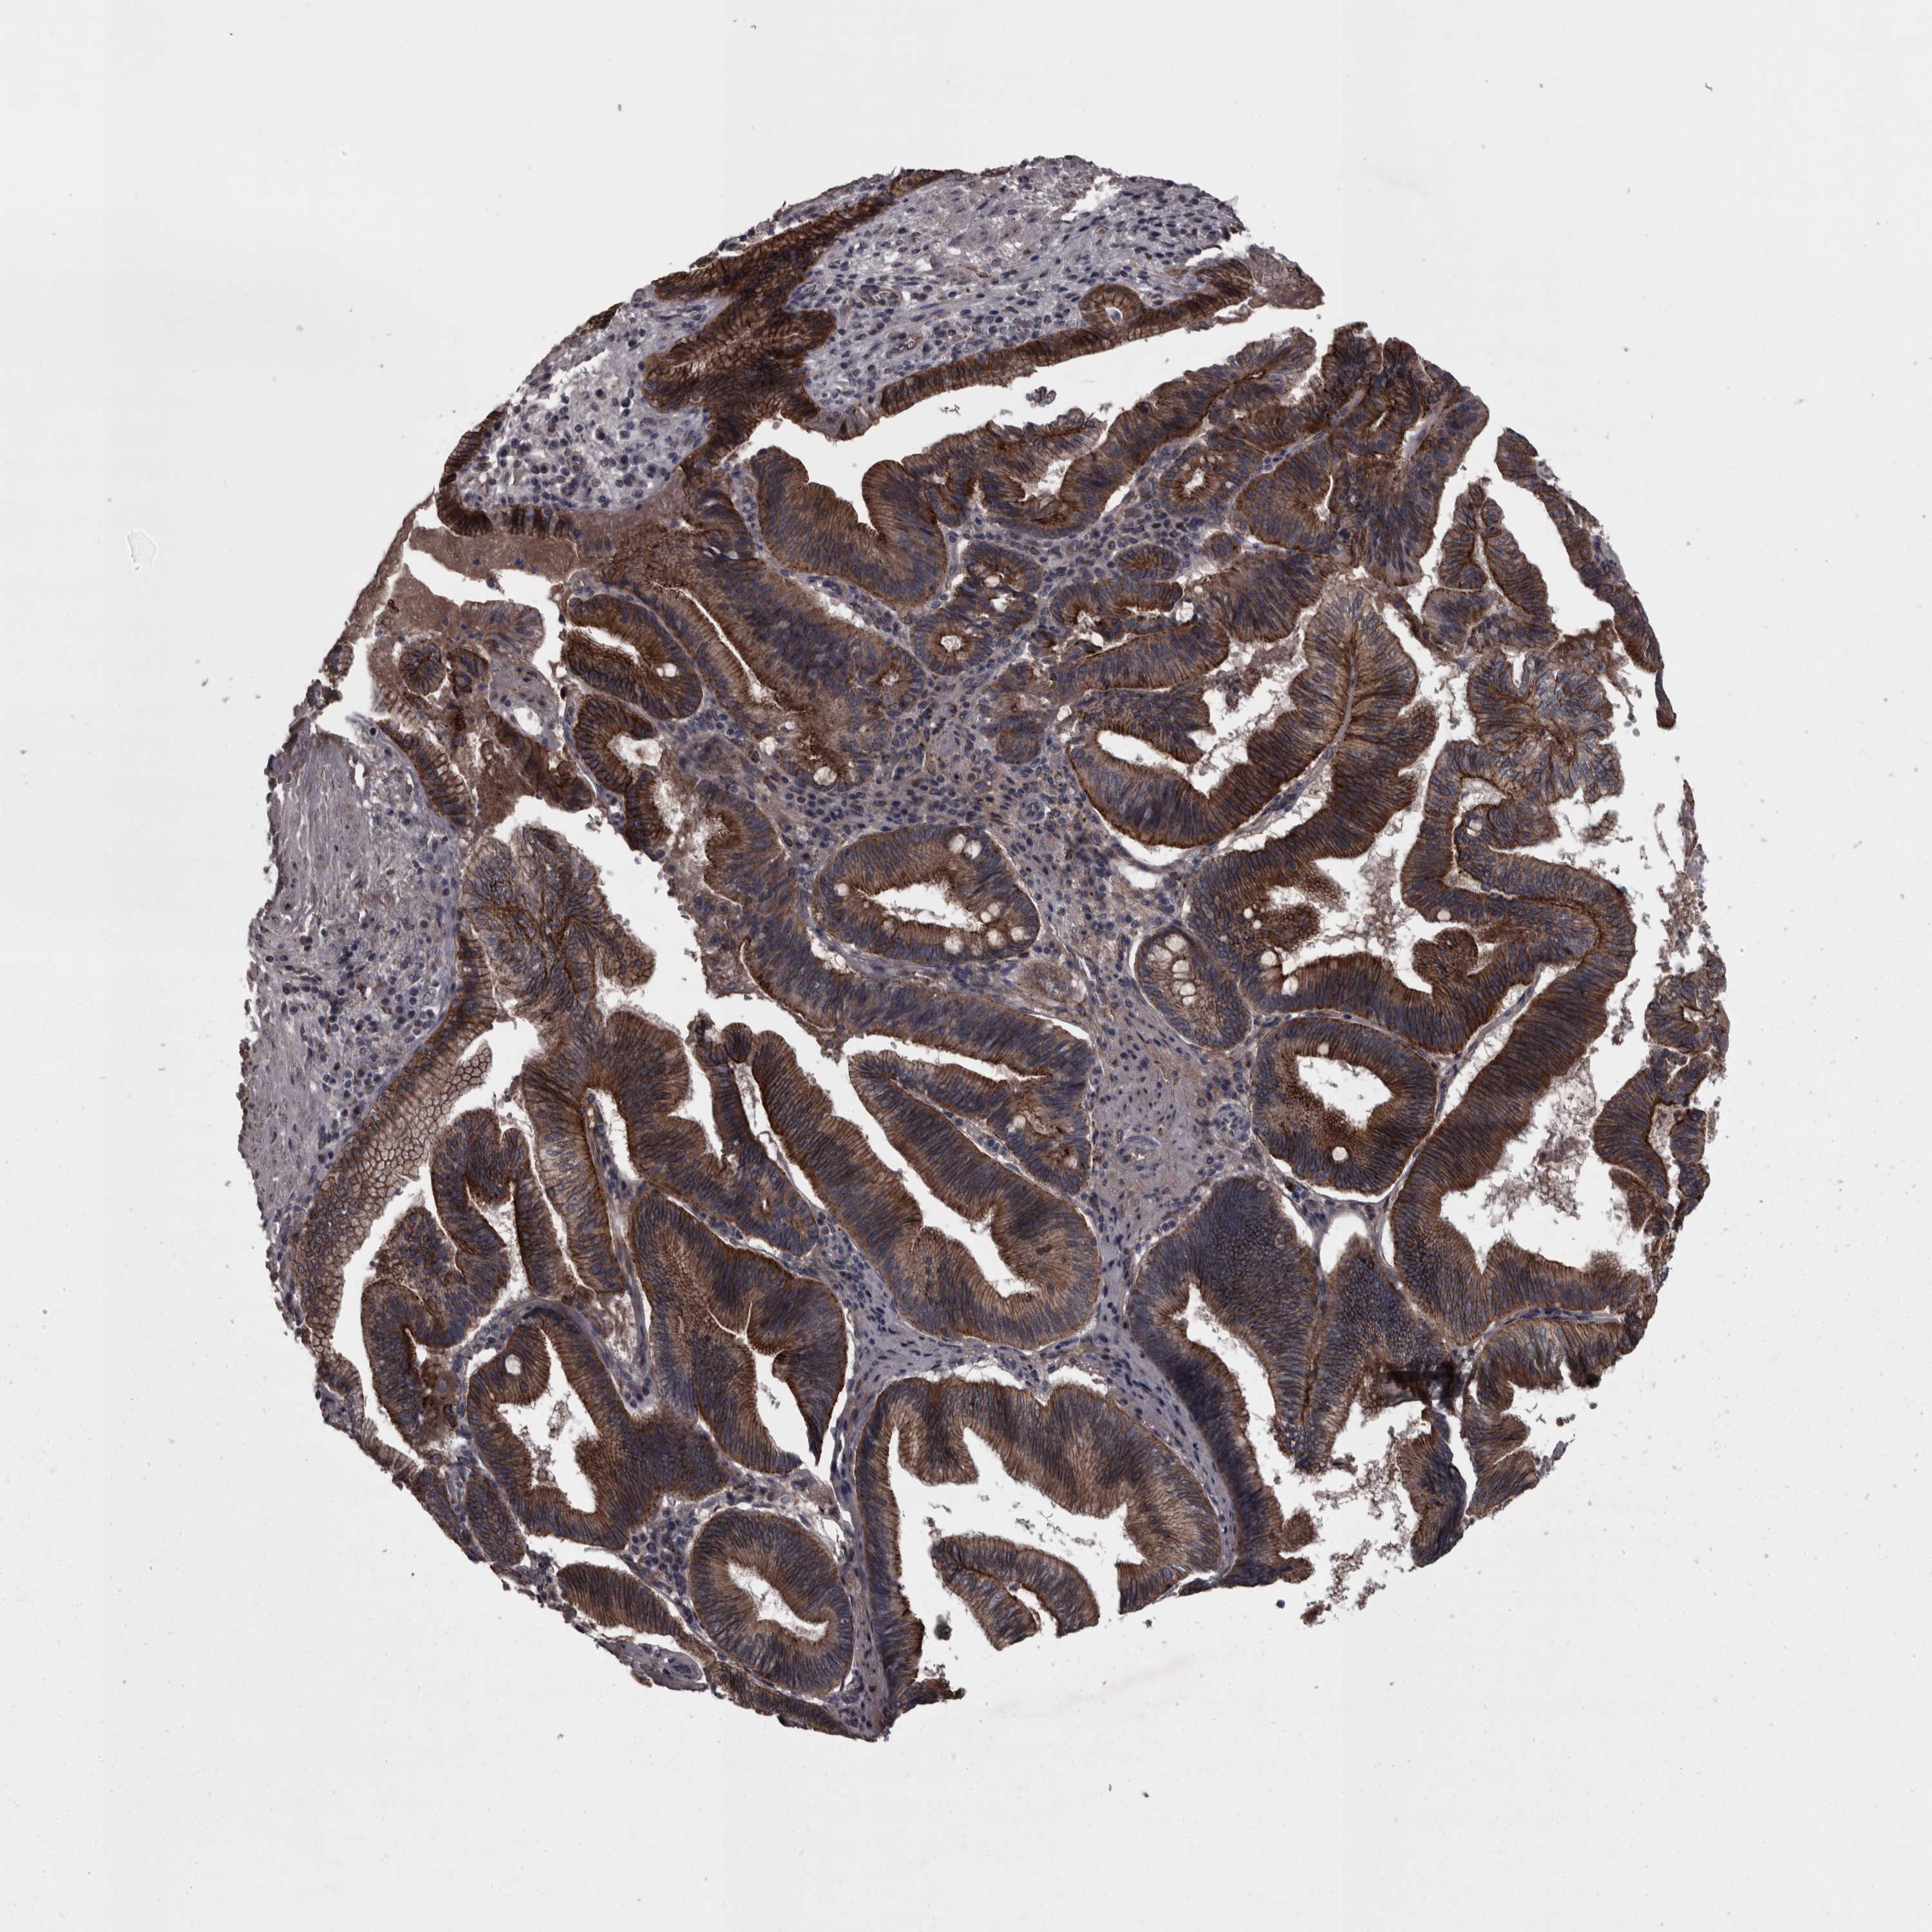

PANCREATIC CANCER - Protein expressioni

A mouse-over function shows sample information and annotation data. Click on an image to view it in a full screen mode. Samples can be filtered based on level of antibody staining by selecting one or several of the following categories: high, medium, low and not detected. The assay and annotation is described here.

Note that samples used for immunohistochemistry by the Human Protein Atlas do not correspond to samples in the TCGA dataset.

Antibody stainingi

Antibody staining in the annotated cell types in the current human tissue is reported as not detected, low, medium, or high, based on conventional immunohistochemistry profiling in selected tissues. This score is based on the combination of the staining intensity and fraction of stained cells.

Each image is clickable and will lead to virtual microscopy that enables deeper exploration of all samples and also displays staining intensity scores, fraction scores and subcellular localization as well as patient and tissue information for each sample.

Antibody HPA026817

Staining

High

Medium

Low

Not detected

Intensity

Strong

Moderate

Weak

Negative

Quantity

>75%

75%-25%

<25%

None

Location

Nuclear

Cytoplasmic/membranous

Cytoplasmic/membranous,nuclear

Adenocarcinoma, NOS

Adenocarcinoma, metastatic, NOS